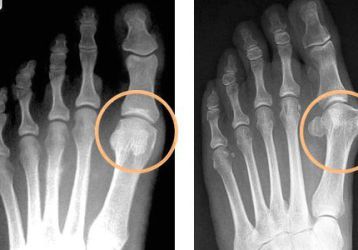

Артрит пальцев ног: симптомы и способы лечения

Лечение артрита пальцев ног. Способы медикаментозного воздействия. Диета для облегчения состояния. Терапия большого пальца.